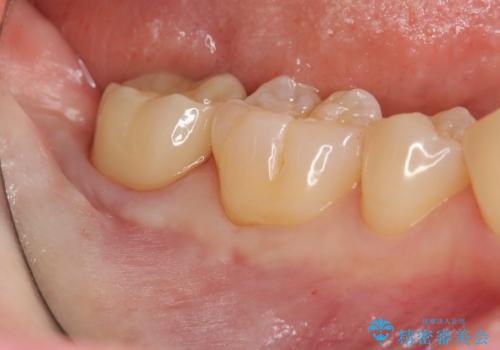

親知らずを起因とする虫歯治療

大きい虫歯 根管治療〜オールセラミッククラウン